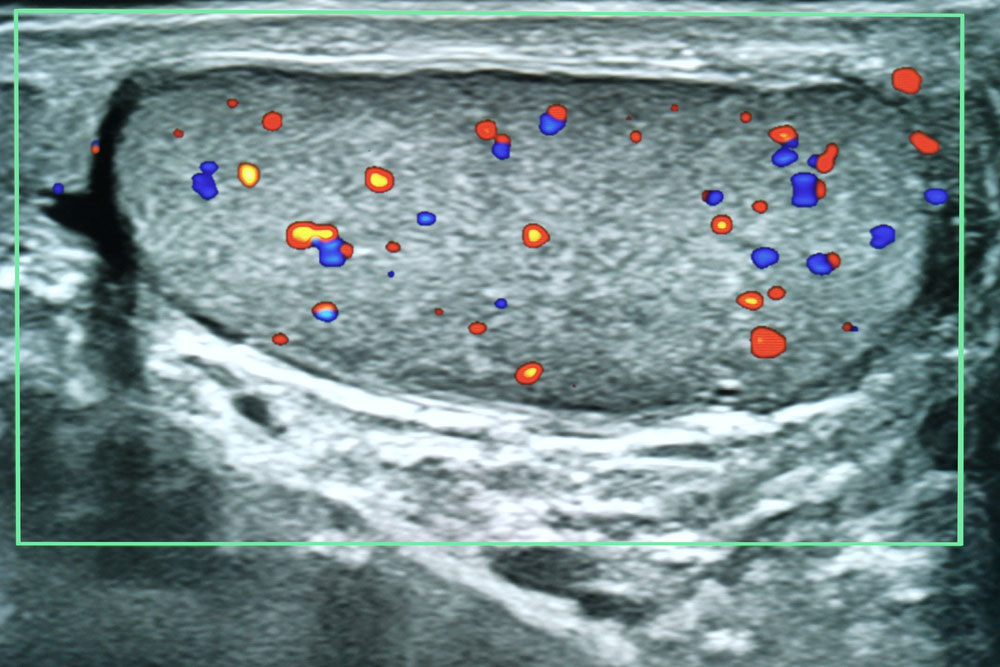

Pored toga, ultrazvuk testisa je koristan u proceni dotoka krvi u testise. Smanjen protok krvi može ukazivati na stanja poput torzije testisa ili varikokele, koja zahtevaju hitnu medicinsku pomoć.

Sve u svemu, ultrazvuk testisa je dragoceno sredstvo u dijagnostici i praćenju različitih stanja koja utiču na testise. Pruža detaljne informacije o strukturi, protoku krvi i svim prisutnim abnormalnostima, pomažući zdravstvenim radnicima da postave tačne dijagnoze i razviju odgovarajuće planove lečenja.

Pregled se sprovodi koristeći visokofrekventni ultrazvučni aparat koji omogućava precizno vizualiziranje svih delova testisa. Doktor Rončević pridaje posebnu pažnju na identifikaciju eventualnih promena, kao što su ciste, tumori ili upale, te prati njihovu veličinu, oblik i lokalizaciju.